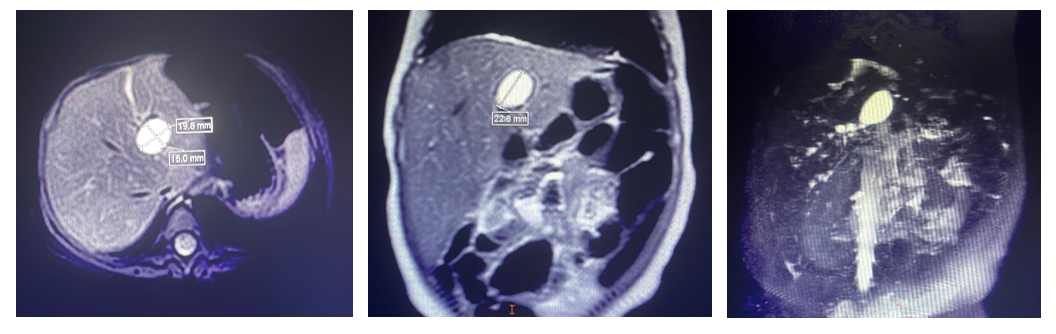

住进普通(新生儿)外科病房后,医生为久久完善了检查,磁共振胰胆管造影显示:肝门区见类圆形异常信号灶,2.3×2.0×1.6cm,右侧见多个小圆形异常信号灶。这些扩张的胆管,提示着因为反复的胆管炎症导致远端原本通畅的胆道变得狭窄甚至闭锁了。

二次手术前MRI、MRCP结果:肝门区见类圆形异常信号灶;右侧见多个小圆形异常信号灶